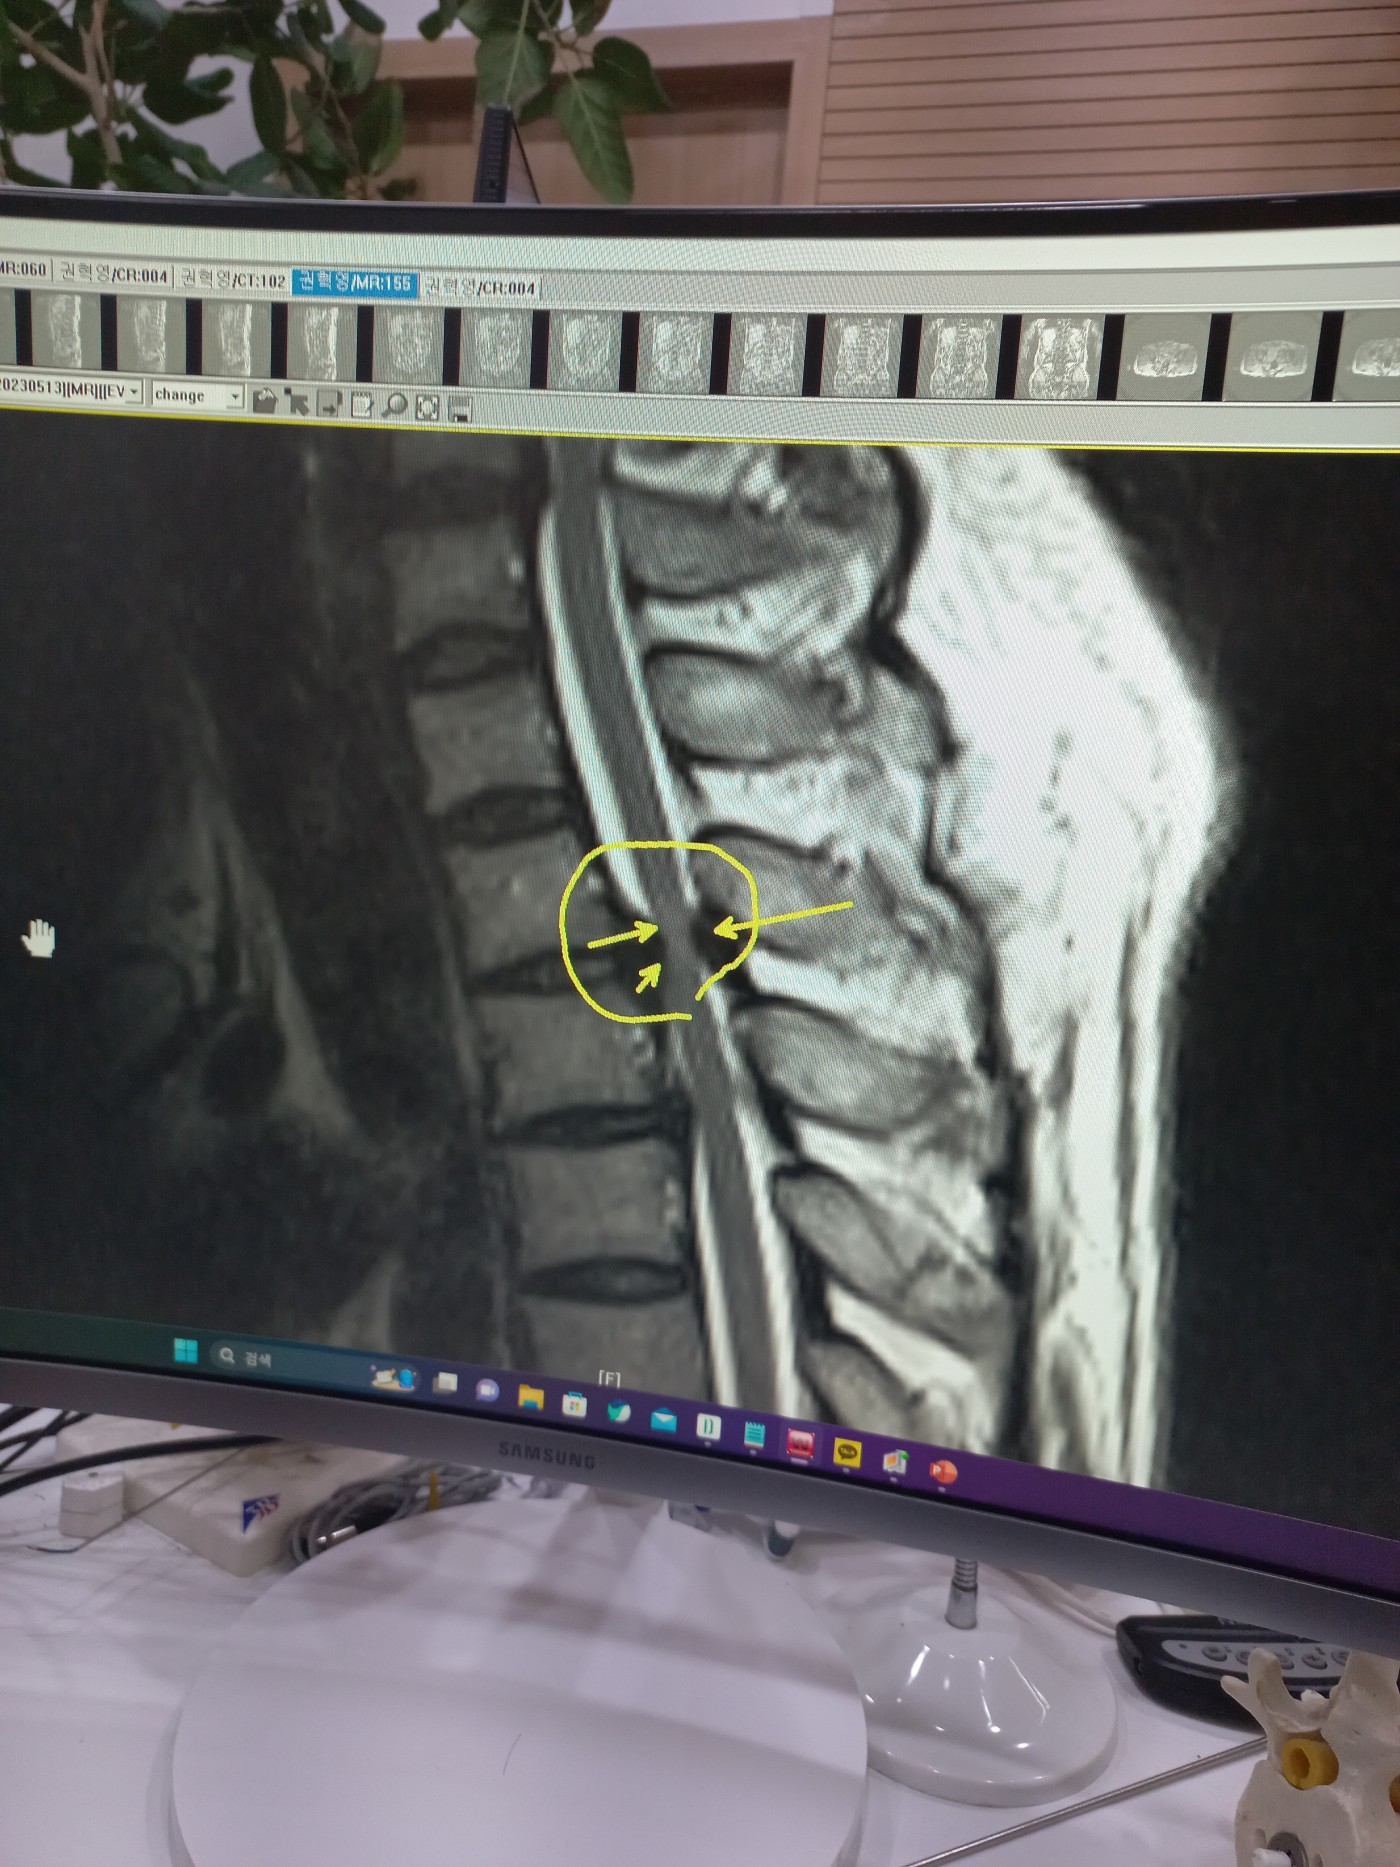

경추, 훔추 후종인대골화

경추,흉추 후종인대 골화증인데 수술적 치료를 받아야 한다고 합니다. 서울 삼성병원

수술후에에도 다리가 시리고 저리는 증상은 호전되지않고 더이상 나빠지지는 않는다고 합니다.

현재  양쪽 다리가 많이 시리고 힘이없어서 걸어만 다니고 뛰거나  하는 운동은 못하고 있는 상태입니다